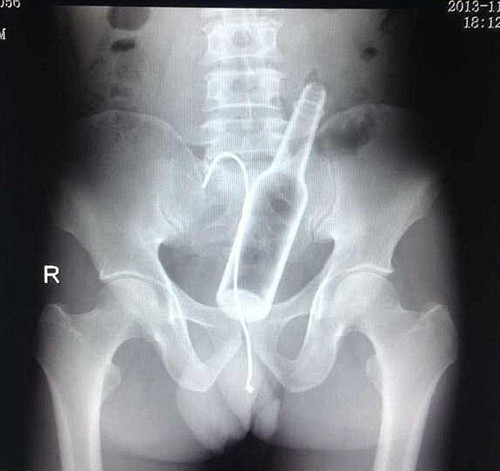

Trong lúc “tự sướng”, người đàn ông này vô tình để chiếc máy rung đi sâu vào cơ thể. Dù vậy thay vì đến các cơ sở y tế gần nhất để lấy dị vật, anh ta lại cố gắng tự lấy máy rung bằng một chiếc kẹp salad khiến nó cũng nằm lại trong đó.